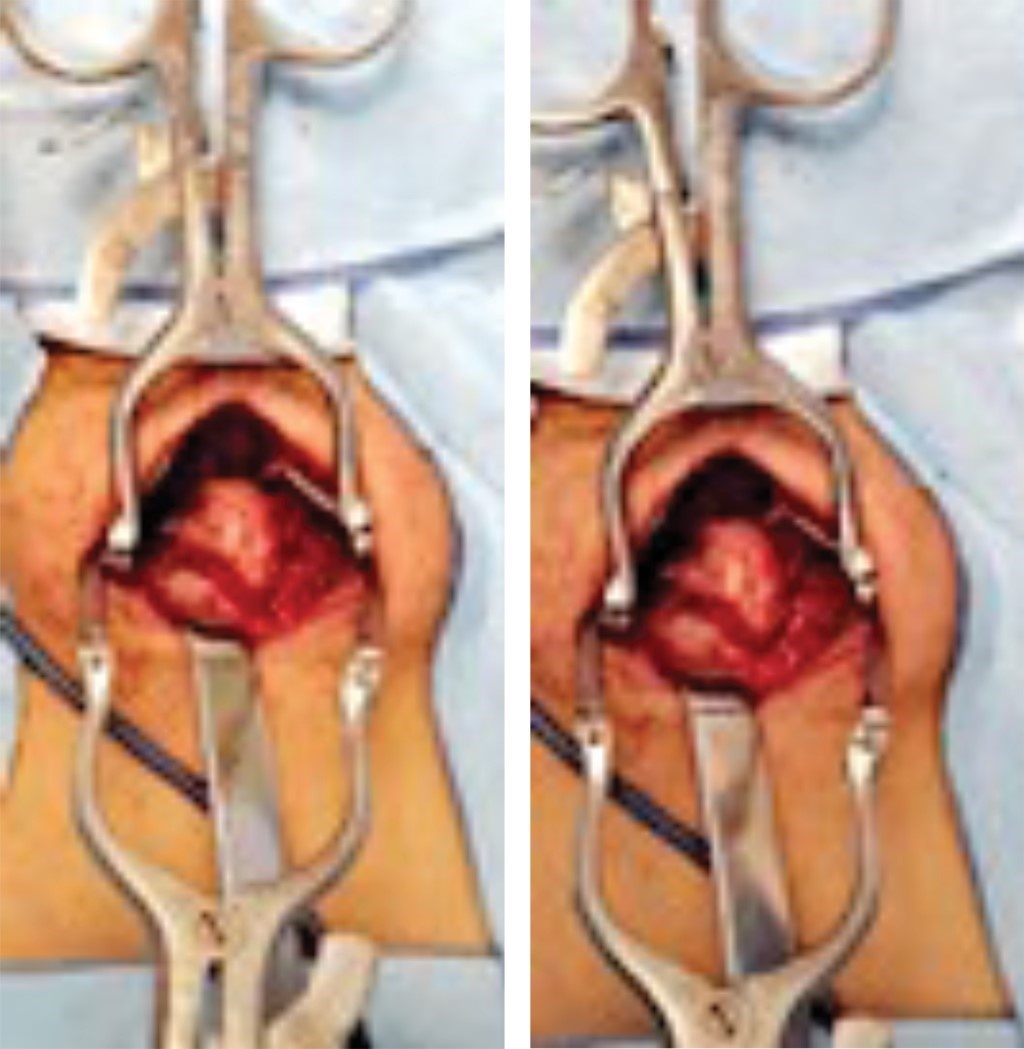

Se realiza biopsia escisional de tumoración mediante abordaje posterior en columna cervical (Figura 5), se observa una lesión sólida de aproximadamente 15 × 20 mm, sin infiltración de tejidos adyacentes y sin datos de reacción perióstica, cortical y bordes bien definidos, base en lámina derecha de quinta vértebra cervical, que verifica no interferencia en movilidad de articulación proximal y distal, la lesión se reseca desde su base permitiendo margen de 5 mm, sin invasión intradural y sin afectar estabilidad de lámina vertebral, la cual se observa íntegra, por lo que no requiere estabilización quirúrgica. Se envía muestra a estudios histopatológicos.

Figura 5